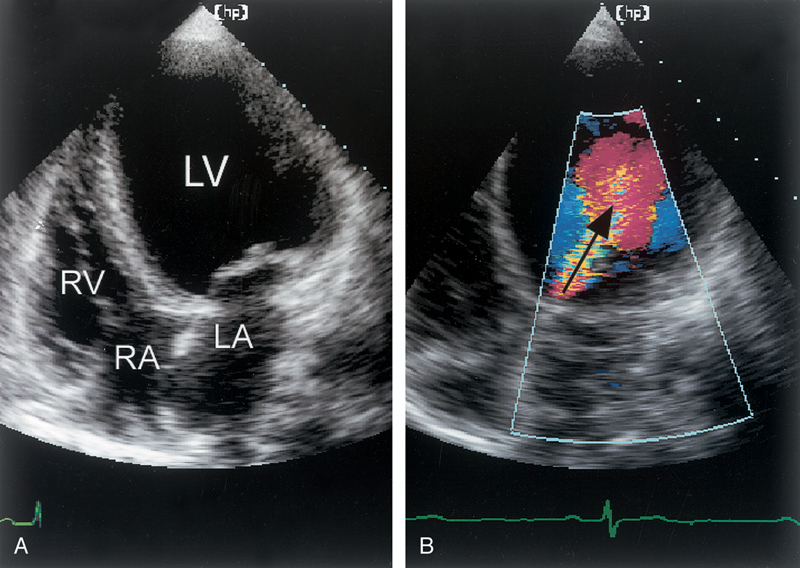

فحوصات تشخيصية لبعض امراض القلب والشرايين التاجية